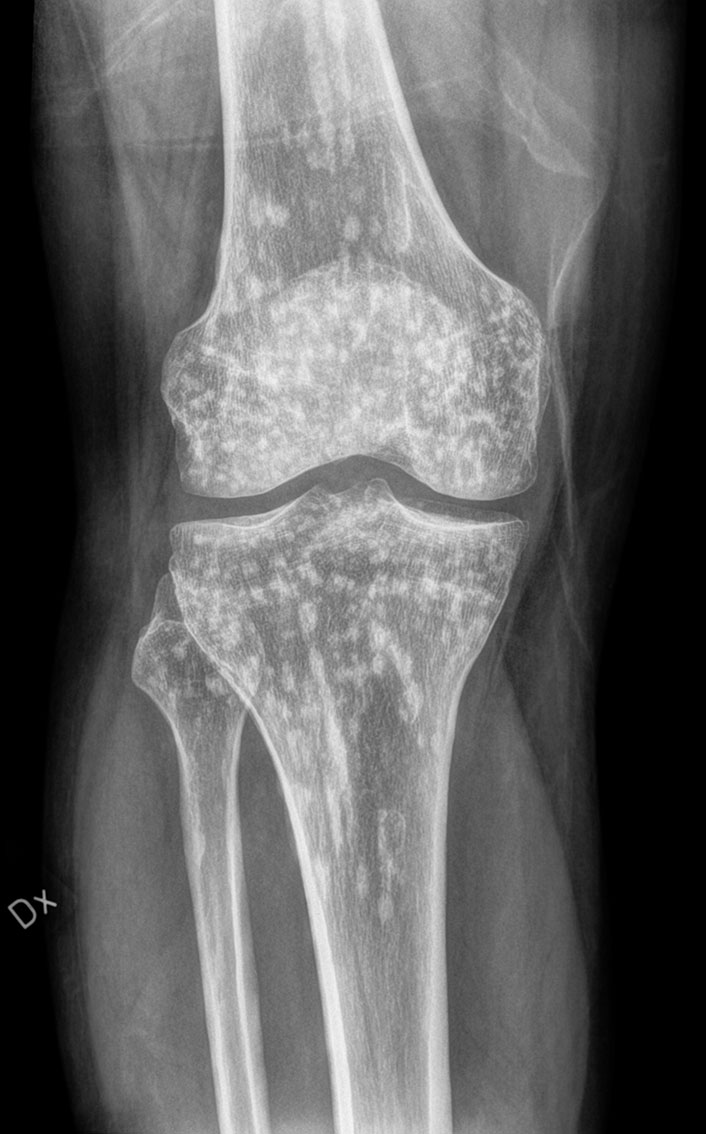

Røntgenbildet viser multiple flekkvise sklerotiske lesjoner i både femur, tibia og fibula. Bildet ble tatt da en tidligere frisk mann i slutten av trettiårene oppsøkte ortopedisk skadepoliklinikk etter et fall med vridning av kneet. Han kunne på dette tidspunktet ikke belaste det vonde benet, og opplevde at en bøyd knestilling ga mindre ubehag. Pasienten ble henvist til akutt røntgen for å utelukke brudd. Røntgenfunnet er forenlig med osteopoikilose og tolkes som et tilfeldig funn, ikke relatert til pasientens aktuelle skade. Pasientens smertetilstand i kneet gikk over av seg selv uten aktive tiltak.

Osteopoikilose er en benign autosomal dominant tilstand man kan finne i skjelettet, karakterisert av områder med små sklerotiske lesjoner (1). Osteopoikilose finnes oftest i de lange rørknoklene, i hender og føtter, i bekkenet og i skulderbladene. Tilstanden er sjelden, med en insidens på 1: 50 000 (2). Den oppstår like hyppig hos kvinner og menn, og gir vanligvis ingen symptomer. Tilstanden progredierer ikke til malignitet, og påvirker ikke skjelettkvaliteten. Det er ikke nødvendig med MR-undersøkelse for å stille diagnosen. På en eventuell MR vil lesjonene ha lav signalintensitet, både på T1- og T2-vektede bilder, og dermed fremstå som svarte flekker.